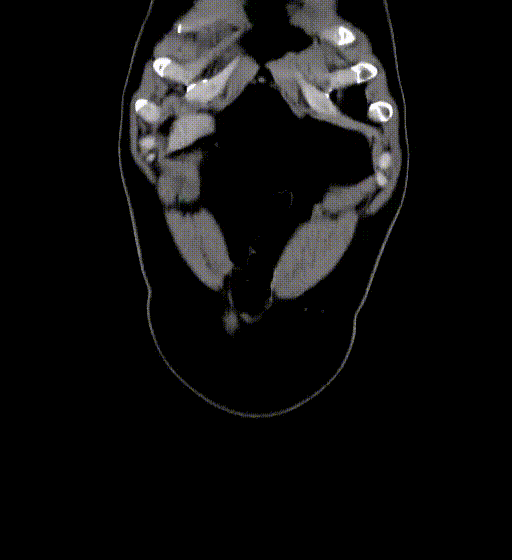

图为:入院全腹部CT及增强扫描

图为:尝试腔内回收滤器,滤器无法回收入鞘,下腔静脉缩窄明显